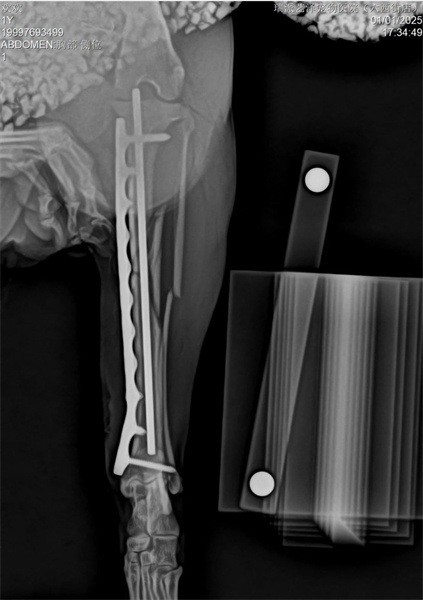

右肱骨幹橫形骨折採外側入路,全開放性接觸固定頭側及外側雙 骨板.橫向骨折板孔用頭側接骨板上的加壓螺絲縮小。

由於是PRCL鎖定接骨板系統,力求接骨板塑形完美,但不要刻意追求塑形絕對完美

脛骨採用內側MIPO手術入路,盡可能保護軟組織,並以髓內釘及橋接骨板固定。

脛骨採用PRCL8mm接骨板和2.5mm穿刺針,確保近端和遠端至少有兩枚螺絲